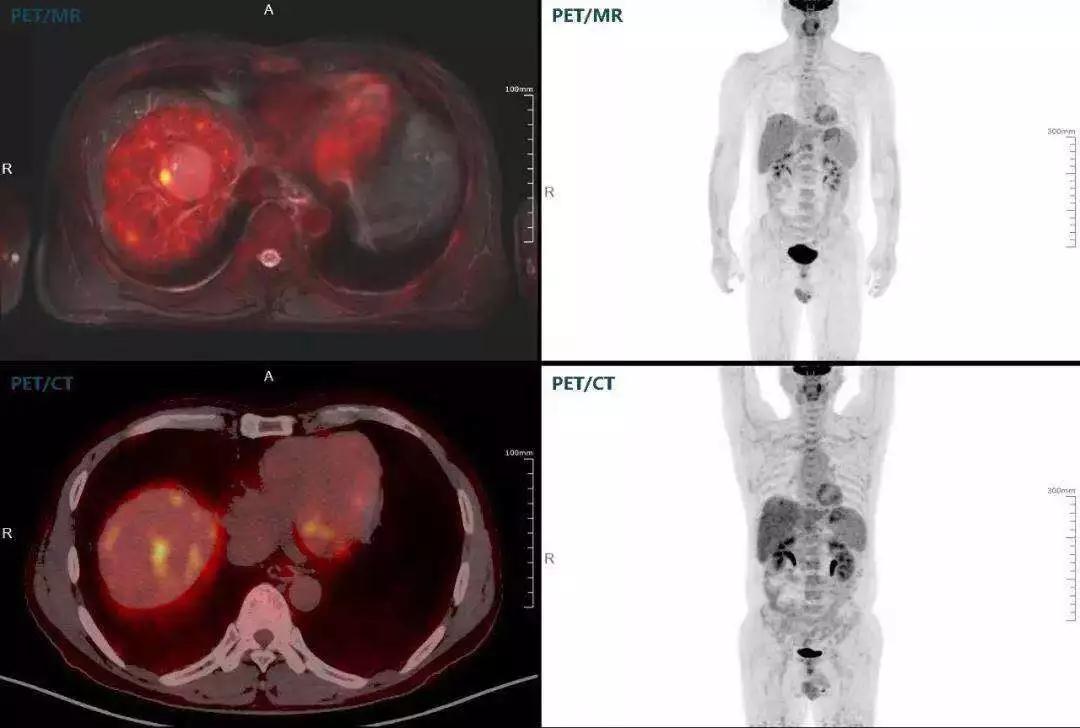

(對于同一例肝臟惡性腫瘤,PET-CT與PET/MR成像對比??梢钥吹?,聯(lián)影PET/MR圖像對腫瘤邊界和FDG高濃聚區(qū)域清晰顯示。)